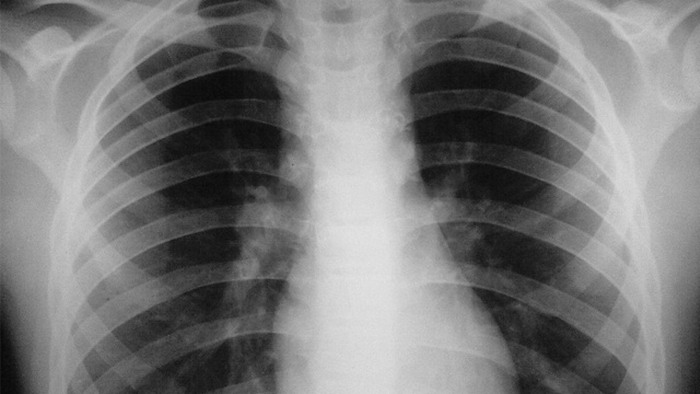

لمقاومة هذا الداء، من خلال إعادة تأهيل مراكز تشخيص وعلاج السل والأمراض التنفسية

وتعزيزها بأجهزة للتشخيص البيولوجي المعتمد على تحليل الحمض النووي وأجهزة رقمية للكشف

بالأشعة السينية مع ضمان مجانية التكفل بكل المرضى، فضلا عن تحقيق تقدم كبير من خلال